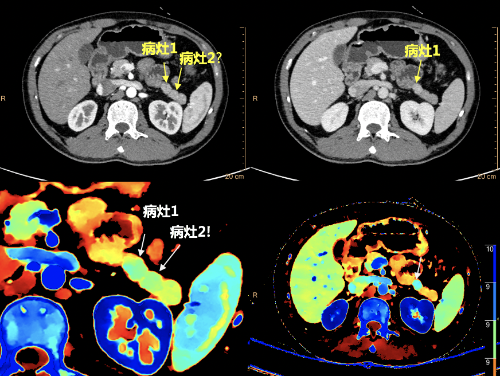

金女士经过CT扫描后,在常规CT图像中胰体部隐约可见的病灶,经过重建40keV虚拟单能量图像、碘密度图等多参数图像,能量CT多参数成像精确的定位并显示出胰腺内部确有“真凶”(图1)。随后金女士被转到了胰腺外科手术,进行了“胰体尾部切除术”,手术病理证实确实为胰岛素瘤。手术后金女士血糖、胰岛素恢复正常水平,从此脱离头晕眼花之苦。

(图1)